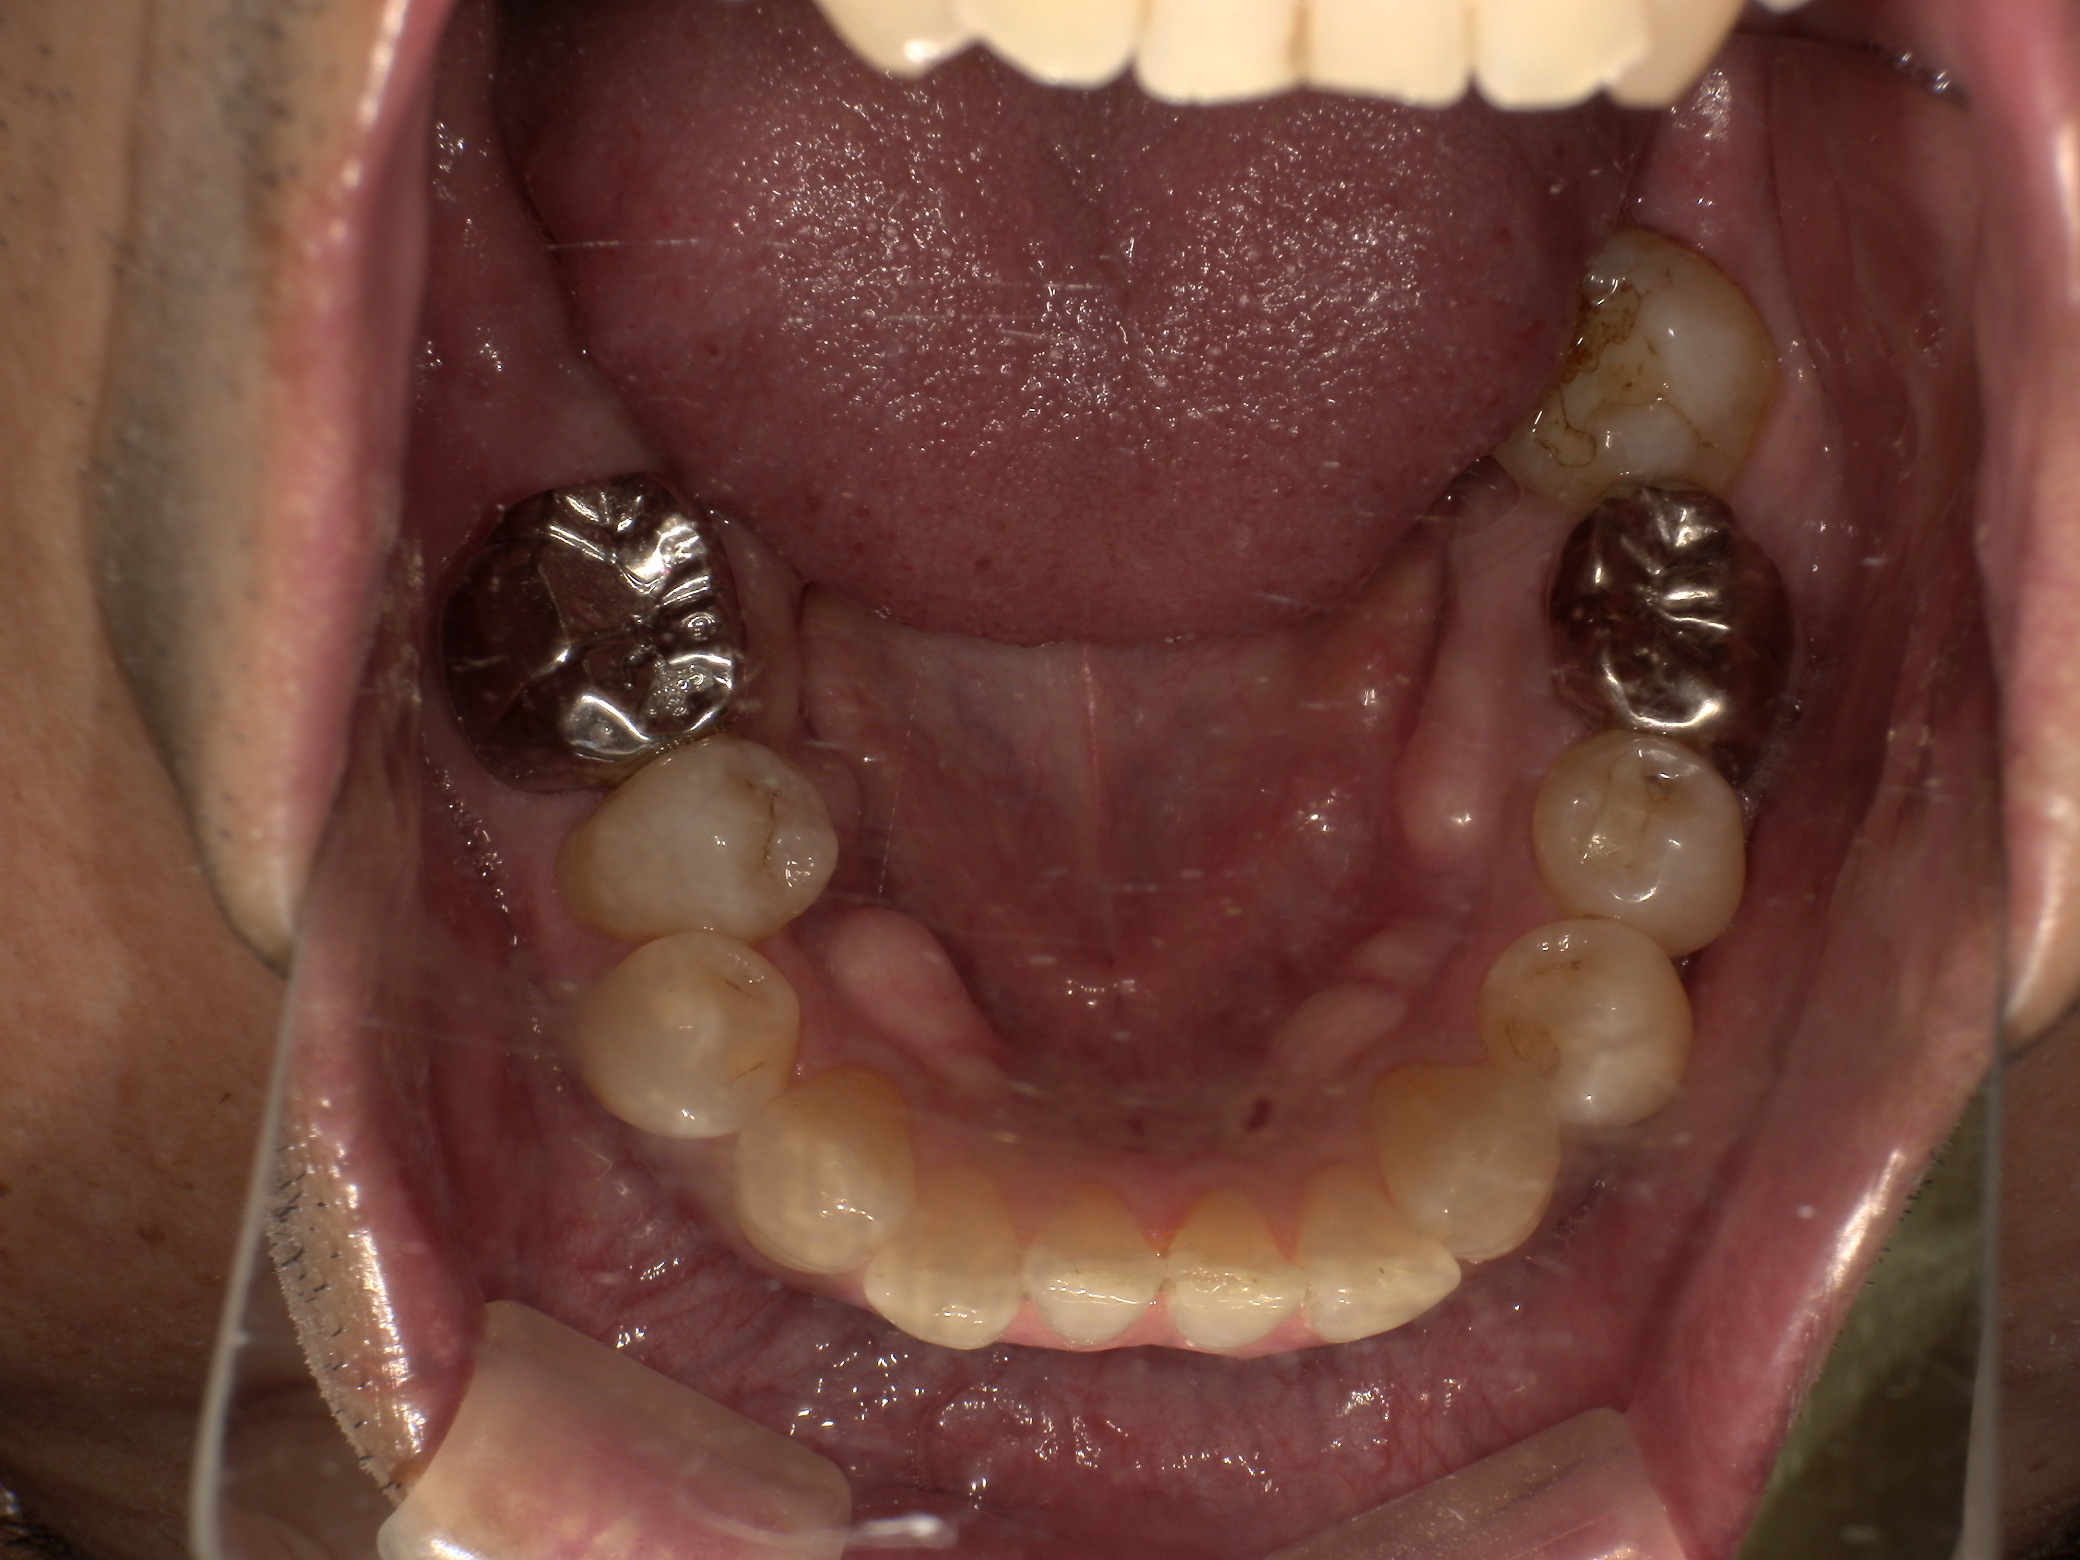

• インプラント

ソケットプリザベーション&インプラント症例|右下の奥歯が何もしなくても痛い

インプラント症例|右下の被せものがとれてしまった

右下インプラントブリッジ、左下インプラント症例

左下に歯の移植かインプラントか相談をしたい(インプラント症例)

入れ歯が使えなくて他の方法を考えている(インプラント症例)